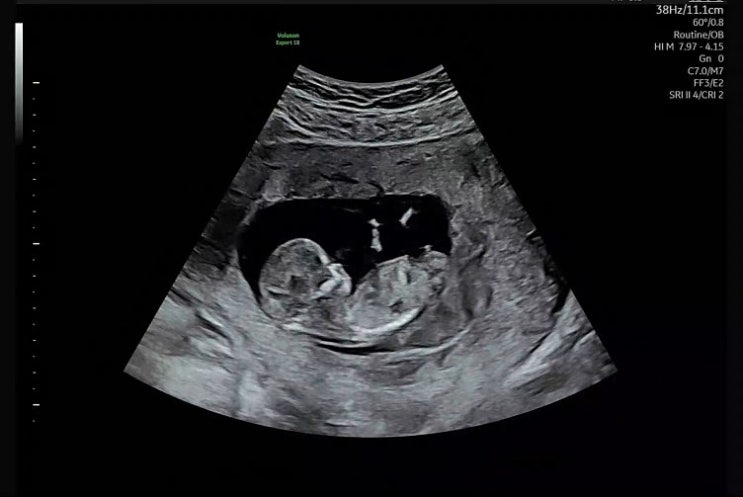

[12주 0일]1차 기형아검사 목투명대 , 임신 12주 배크기

1차 기형아검사 목투명대 검사 임신 12주 배크기 2025년 2월 4일 12주차 0일 꼼이 1차 기형아 검사를 하러 ...